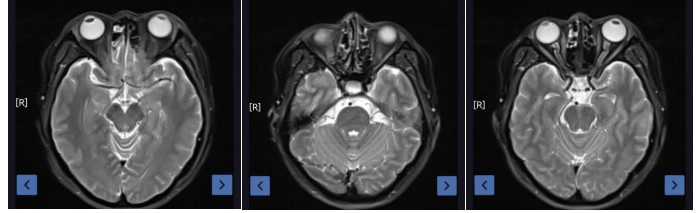

Results: The treatment was effective, with a partial response (PR) at the end of radiotherapy and 3 months post-treatment, and a complete response (CR) at 2 years post-treatment. The acute radiation skin injury grade was 1 according to RTOG criteria, and the adverse event grade was 1 according to CTCAE-V5.0. No ocular toxicity, such as vision loss or visual impairment, was observed 2 years after radiotherapy.

Figure 2: Post-treatment at 2 years (complete resolution of the lesion)